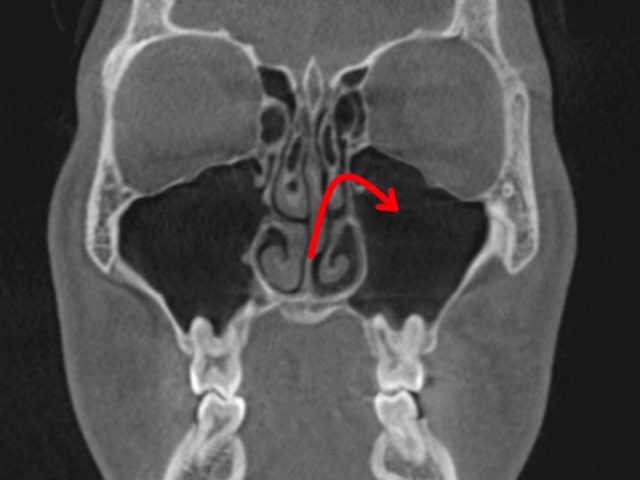

歯性上顎洞炎になりにくい人

上は、上の大臼歯の歯根と、

上顎洞の距離がある方です。

もし、歯根が化膿しても、

炎症は、上顎洞へは、波及しにくいでしょう。

この様な方は、

歯性上顎洞炎には、なりにくいと思われます。